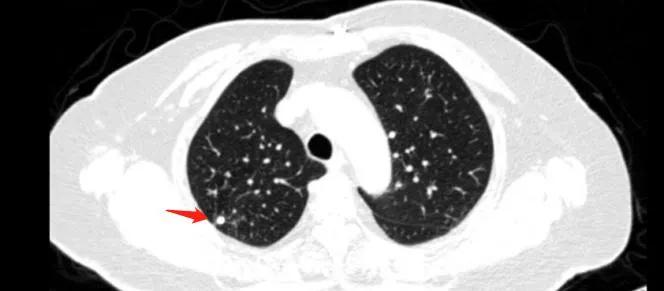

肺结节是指肺部实质内类圆形、境界清楚、直径小于等于3cm的软组织病灶。 根据结节的密度,可以分为实性肺结节、纯磨玻璃结节和混合磨玻璃结节。其中,混合磨玻璃结节(也被称为“荷包蛋”)的恶性几率最大,其次是纯磨玻璃结节(“鸡蛋清”),而实性结节(“水煮蛋”)的恶性几率相对较小。

诊断肺结节主要依靠影像学检查,其中 低剂量胸部CT平扫是最常用的筛查方法。 这种检查辐射剂量小,分辨率高,对直径小于1cm的肺结节检出率超过80%。对于直径大于8mm的实性结节或部分实性结节,还可以通过PET-CT检查来进一步评估其良恶性。